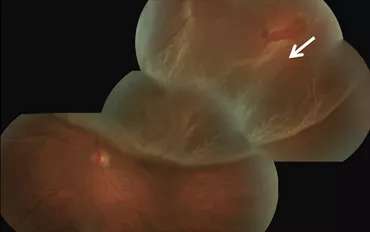

Retinal Detachment

The retina lines the back wall of the eye, and is responsible for absorbing the light that enters the eye and converting it into an electrical signal that is sent to the brain via the optic nerve, allowing you to see.